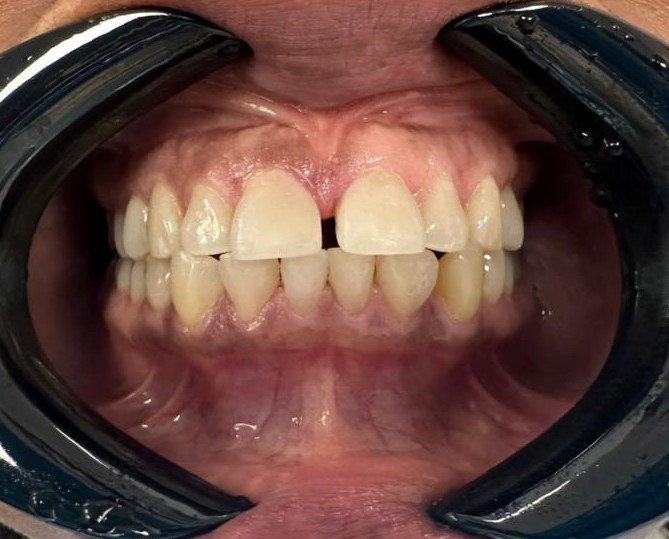

Nel primo pomeriggio del giorno di arrivo sono stati raccolti i dati anamnestici e realizzata un’ortopantomografia digitale di controllo. Sono stati eseguiti record fotografici iniziali (Figura 1) e rimossi i vecchi restauri in composito.

Figura 1 Situazione iniziale prima della rimozione dei vecchi restauri in composito.